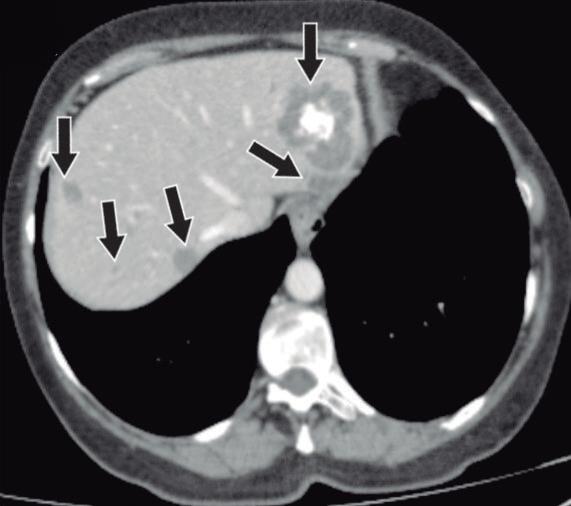

Diagnóstico diferencial con el adenocarcinoma pancreático

La PAI y el ACDP tienen una epidemiología en común, prevaleciendo en pacientes de sexo masculino, adultos, en la 5° y 6° década de la vida. Comparten también una presentación clínica similar correspondiente a ictericia. Si bien la forma difusa de la PAI puede ser diferenciada imagenológicamente del ACDP, su forma focal, no tan infrecuente, representa un desafío complejo y plantea la necesidad imperiosa de diferenciarlo del cáncer. El ACDP presenta típicamente bordes imprecisos, debido a su crecimiento infiltrativo, mientras que en la PAI podemos hallar límites más netos, relativamente mejor delimitados. Es frecuente la invasión local, con compromiso vascular en el ACDP, lo cual suele ser extremadamente infrecuente en la PAI.

En adquisiciones dinámicas post-contraste intravenoso, ambas entidades suelen ser lesiones hipovasculares en fase arterial. El ACDP es un tumor con gran desmoplasia, si bien presenta frecuentemente realce en fases tardías, en la PAI este refuerzo suele ser más pronunciado y persistente. En RM la secuencia de difusión, dada su elevada sensibilidad, puede contribuir en la diferenciación, particularmente por su aspecto y distribución. En la PAI la restricción puede ser multifocal, contribuyendo a identificar focos inflamatorios adicionales que pueden pasar desapercibidos en otros métodos, incluso en otras secuencias de RM. Se ha descripto que la magnitud de la restricción es superior

en la PAI, frente al ACDP, debido al denso acúmulo celular linfoplasmocitario. Un metaanálisis publicado en Radiology en el año 2014 revisó los valores del mapa de coeficiente de difusión aparente en pacientes con lesiones pancreáticas, incluyendo ACDP, tumores neuroendocrinos, pancreatitis aguda, pancreatitis crónica y PAI. De todas las entidades incluidas, la PAI fue la que mostró la media de ADC más baja, correspondiendo a 0,9 x 10-3 mm 2/seg, mientras que el adenocarcinoma mostró una media de 1,3 x 10-3 mm 2/seg. 20 Si bien hipotéticamente podríamos utilizar la determinación cuantitativa para diferenciar ambas entidades, la distribución y morfología de las áreas de restricción a la difusión son de mayor utilidad en la práctica clínica cotidiana.

La evaluación ductal contribuye al diagnóstico diferencial. El ACDP provoca obstrucción abrupta del conducto pancreático, existiendo gran dilatación proximal al tumor y atrofia del parénquima distal. En los tumores de la cabeza del páncreas se obstruye no solo el conducto pancreático sino también el conducto colédoco ocasionando una gran dilatación de la vía biliar. En la PAI las estenosis son más largas o eventualmente múltiples, solemos hallar el signo del conducto penetrante, visualizando la señal ductal transcurriendo por el sitio de la lesión. A diferencia del ACDP, en la PAI focal la dilatación pre-estenótica del conducto suele ser muy leve, habitualmente sin dilatación de ramas laterales y no se asocia a la atrofia del páncreas distal.21,22

Figura 10. Diagnóstico diferencial entre PAI y ACDP

10a 10b

10a. TC con contraste, fase parenquimatosa pancreática: Pancreatitis autoinmune. Lesiones hipoperfundidas, multifocales, de bordes relativamente definidos, sin expansión ni deformación de los contornos pancreáticos (flechas blancas). Existe dilatación del conducto pancreático principal, pero es leve y no se asocia con atrofia del parénquima del páncreas distal (flechas amarillas). 10b. TC con contraste, fase parenquimatosa pancreática: Adenocarcinoma ductal. Lesión hipovascular, única, de bordes imprecisos, aspecto infiltrativo (flechas blancas). Amputación abrupta del conducto pancreático principal en el sitio de la lesión, con dilatación ductal proximal a la obstrucción e hipotrofia del páncreas izquierdo.

Tabla 2.

PAI

Morfología

Contornos netos, relativamente bien delimitados.

Sin atrofia del parénquima distal

ACDP

Contraste endovenoso

RMN. Difusión

Invasión local

Evaluación ductal

Hipovascular en fase arterial

Intenso realce en fase tardía

Intensa restricción difusa o multifocal

Infrecuente

Estenosis largas y/o múltiples

Signo del conducto penetrante

Leve dilatación pre-estenotica

PAI: Pancreatitis autoinmune. ACDP: Adenocarcinoma de páncreas.

Contornos imprecisos

Crecimiento infiltrativo

Atrofia del parénquima distal

Leve realce en fase tardía

Restricción focal

Frecuente

Obstrucción abrupta

Gran dilatación pre-estenotica